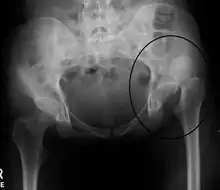

Dislocation of the left hip, secondary to developmental hip dysplasia. Closed arrow marks the acetabulum, open arrow the femoral head.